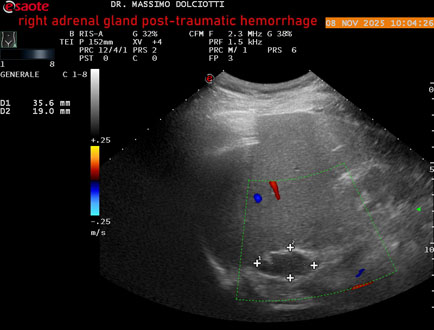

Data inserimento: 10/11/2025

Ecografia del: 08/11/2025

Strumento: Esaote MyLab Eight

Sonda: Convex Multifrequenza 1-8 MHz

Età Paziente: M 49 anni

Motivazione dell'esame: follow up per emorragia al surrene destro post-traumatica (incidente stradale).

Commento all'esame: le immagini ed il video documentano in sede surrenalica destra, formazione ipo-anecogena, a margini definiti, ovalare, delle dimensioni di 38,6 x 19,7 mm, da ricondurre ad emorragia post-traumatica.

Conclusioni: emorragia post-traumatica al surrene destro (post-traumatic hemorrhage to the right adrenal gland).

Presentazione: Dr. Massimo Dolciotti - Ancona

Elaborazione digitale: Andrea Dini - Ancona